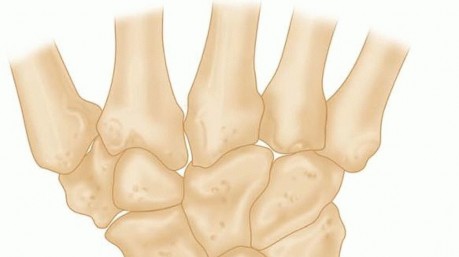

14 MIN READ Operative Treatment of Finger Carpometacarpal Joint Fracture-Dislocations يناير 2023 Read More